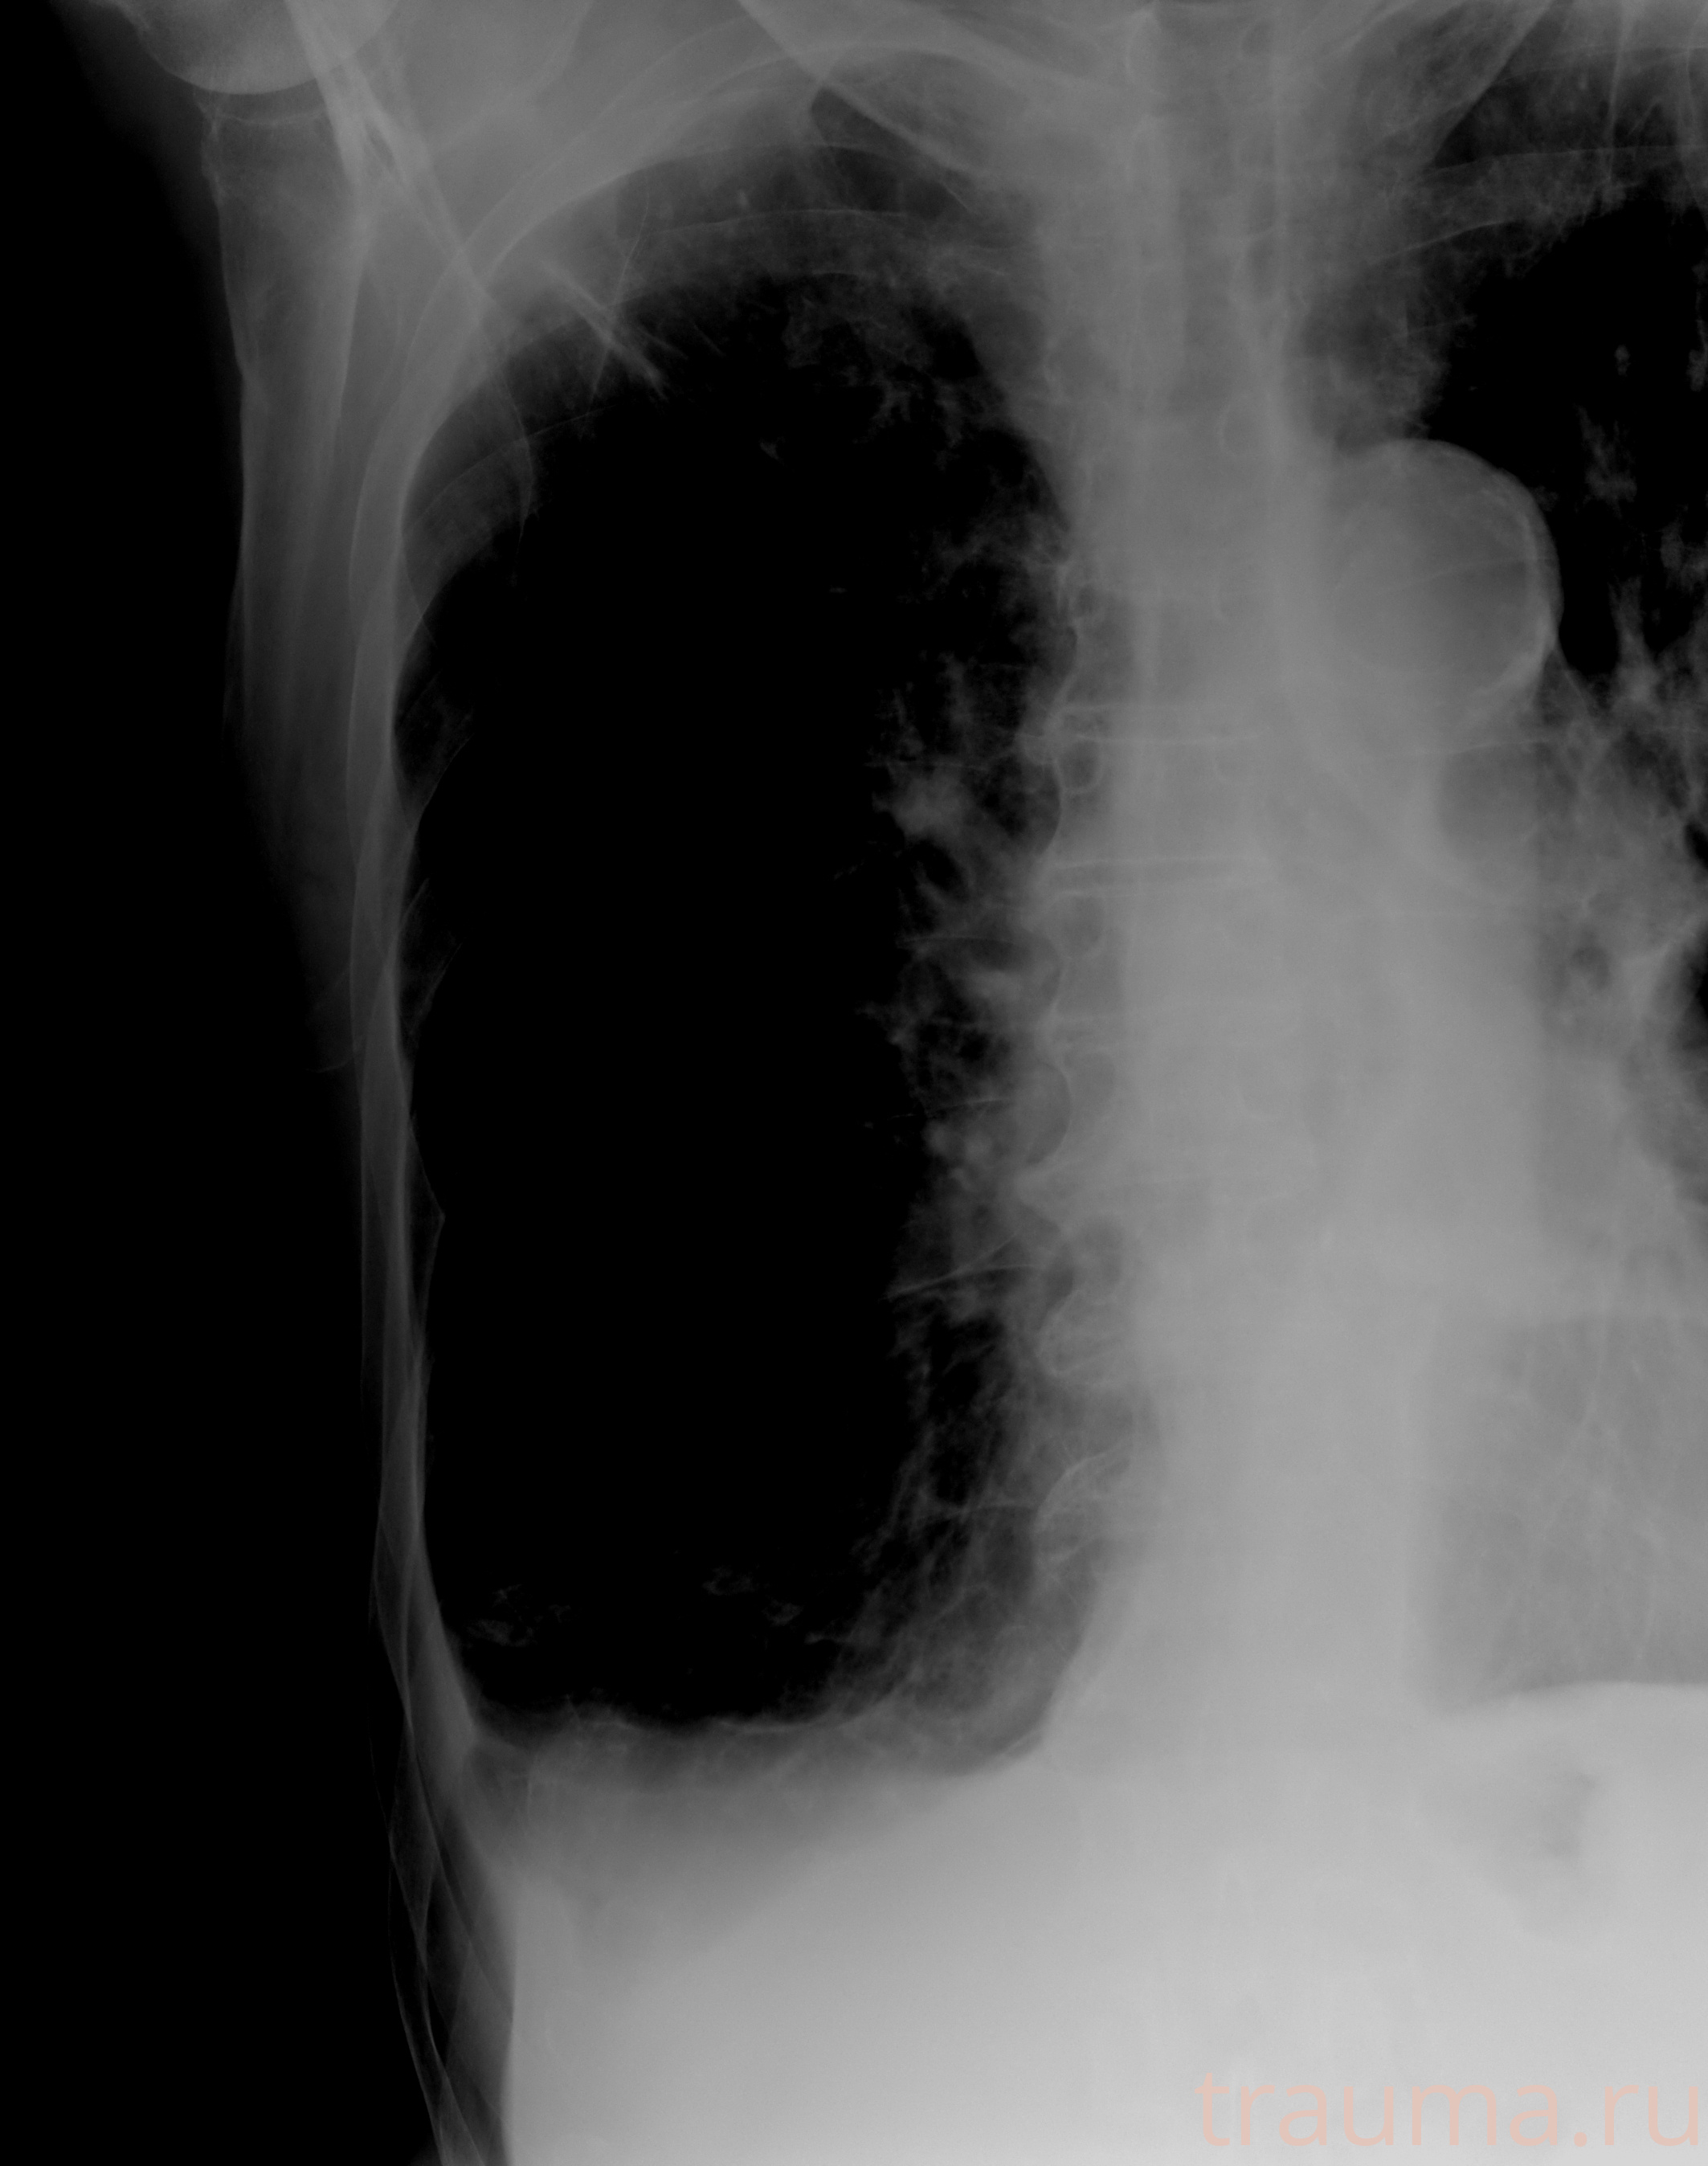

Рентгенограммы

Рентген на дому: по вашему адресу приезжает врач-рентгенолог, травматолог-ортопед с мобильным рентгеновским аппаратом, проводит диагностику травмы или заболевания, делает необходимые рентгенограммы, дает рекомендации по дальнейшему лечению. Получить качественные снимки в домашних условиях возможно благодаря уникальной методике, разработанной МосРентген Центром для института  Склифосовского